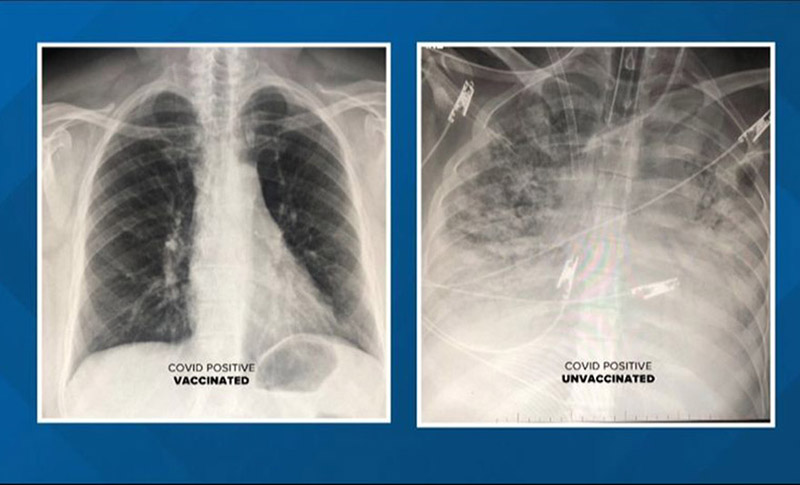

Jasna razlika! Kako izgledaju pluća vakcinisanih, a kako nevakcinisanih “korona pacijenata”

24.10.2021. | 15:24Rendgenski snimci pokazuju uticaj novog korona virusa na pluća pacijenata sa Kovidom-19 – jedan od njih je vakcinisan, a drugi nije.

Doktor objavio rendgen snimak: Evo kako izgledaju pluća vakcinisanih i nevakcinisanih FOTO

10.08.2021. | 13:42Doktor Gasan Kamel iz Univerzitetske bolnice u Sent Luisu pokazao je rendgenske snimke pluća vakcinisanih, i nevakcinisanih pacijenata oboljelih od COVID-a.